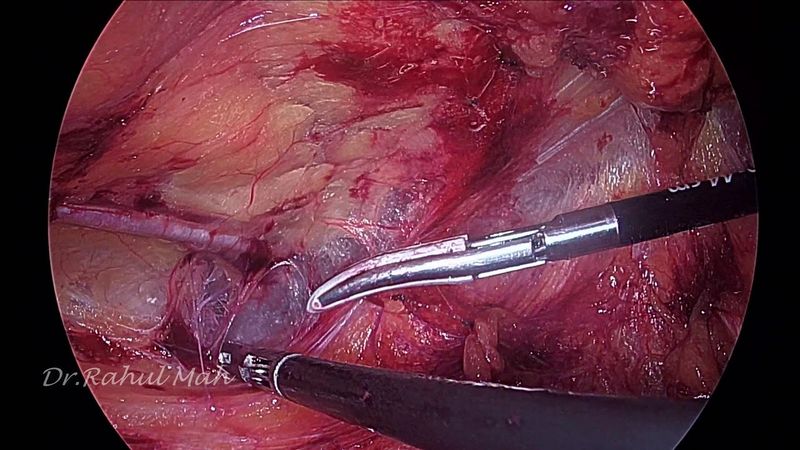

e-TEP RS with midline crossover at Hypogastrium

Download information and video details for e-TEP RS with midline crossover at Hypogastrium

Dr. Rahul MahadarPublished at:

Similar videos: TEP RS with midline crossover at Hypogastrium

eTEP RS with midline crossover in hypogastrium for Primary Epigastric Hernia with divarication